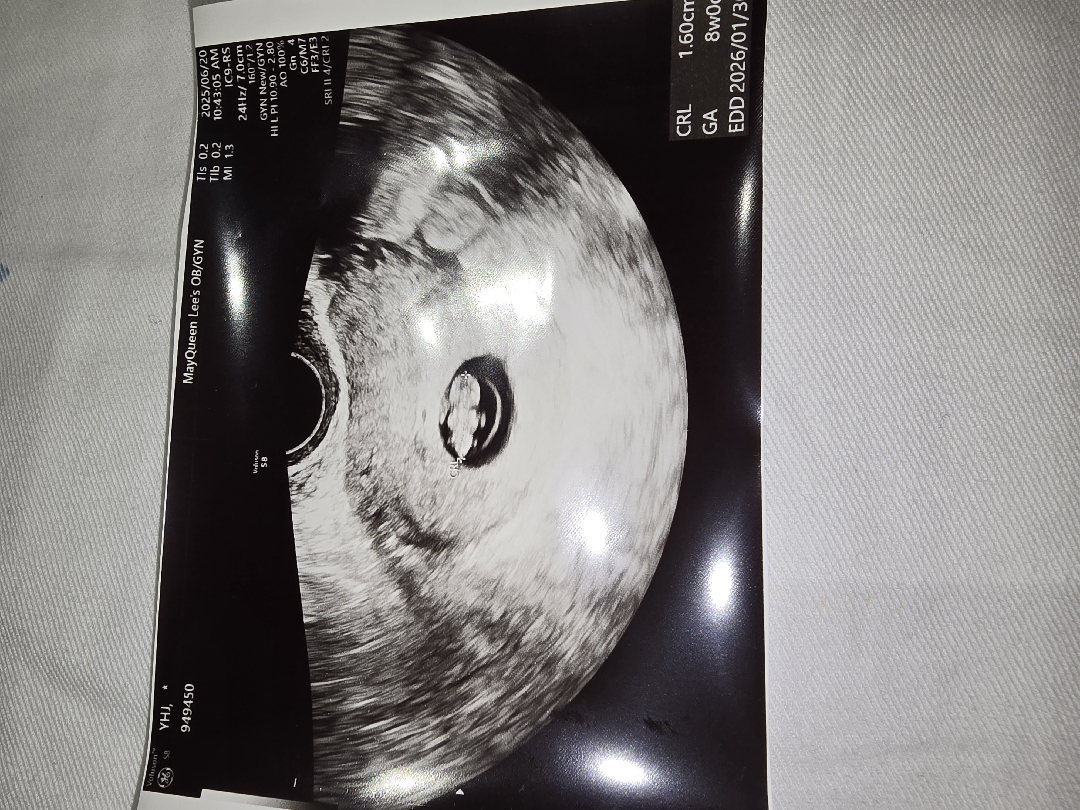

오늘은 7주 6일이에요! 유산방지 주사맞은지 11일?12일? 됐고.. 염증으로 입원생활 중 이에요~ 몸은 아프고 입덧때문에 잘 못 먹지만 딱풀아 잘 커주고 있어줘서 고마워~💕 젤리곰 되고 있는건가요?? 지인이 오 젤리곰됐네? 하는데 응? 했어요😂

초음파상 주수는 8주 더라구요! ㅎㅎ 넘 귀여운거 같아요 ㅋㅋ